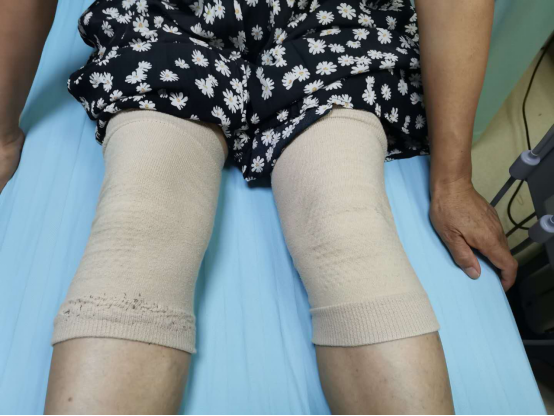

據(jù)了解,王女士雙下肢冷痛伴刺痛已伴隨她20余年,一年四季都要戴著厚厚的護膝。即使現(xiàn)在室外溫度達到35攝氏度以上,她依然護膝不離腿。假如待在空調(diào)房里,她的下肢更是冷痛難忍,讓她無比焦灼。

王女士常年護膝不離腿